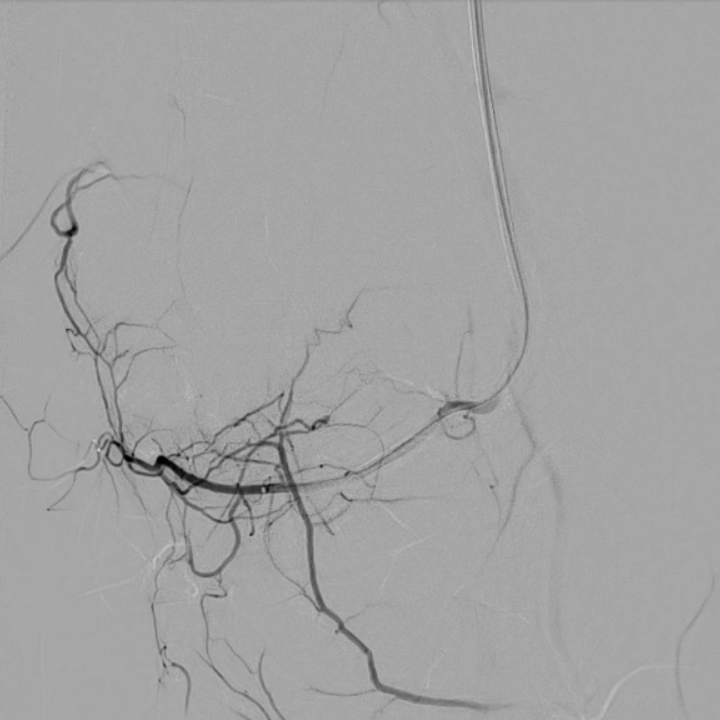

case of the day - 09.02.2026

Kniegelenk

Hier sehen Sie die Bilder vor und nach der Behandlung bei chronischen Kniegelenksbeschwerden. Sehr deutlich ist die geringere Kontrastmittelaufnahme nach Behandlung als Hinweis der verringerten Durchblutung der entzündeten Bereiche zu sehen.

Arteria genicularis inferior lateralis - vor Behandlung

Arteria genicularis inferior lateralis - nach Behandlung